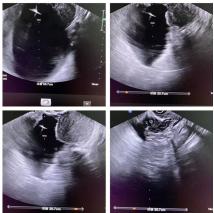

日前,某位腹部不适患者来到淄博市妇幼保健院超声二科就医,值班大夫给患者进行常规检查,惊讶地发现其下腹部有一大小约20×20×10cm巨大囊肿,壁光滑,透声好,大略估测囊液量约2000ml(4斤重),囊壁及周边均未发现明显其他异常超声征象。经综合判断并依据患者主观意愿,医患双方决定选择行操作简便、费用低、创伤小的“阴式超声引导下盆腔囊性肿物穿刺术”来解决这个棘手问题。

经过术前常规会阴部消毒,在阴式超声引导下,医生将一根20cm18G细针巧妙地避开了血管及腹部脏器准确刺入囊肿内,经20分钟左右抽吸操作,共抽出2100ml清亮囊液。因操作无须麻醉,患者与操作医护们在术中一同见到了囊肿由大变小、直至消失的过程,整个过程患者没有感到疼痛等不适。只是“扎了一针”,4斤重的巨大囊肿就消失了,腹部不适症状也随之消除了,而且治疗时间之短、费用之低、效果之理想,完全超出了患者及家人的想象。手术结束后密切观察30分钟无特殊情况,患者满意地自己走出了诊室,且不需要留院观察。术后抽取液被送至病理科进行相关检查,未发现肿瘤细胞,至此整个治疗过程圆满结束。